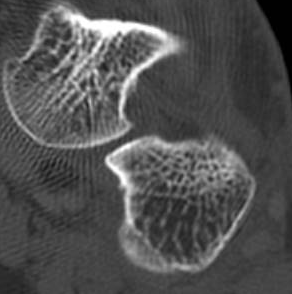

ÄÄÇ»ÅÍ ÃÔ¿µ : Á¾°ñÀÇ °ñÀý , µÎ ºÎÀ§(÷ºÎ ÆÄÀÏ Âü°í)

ÄÄÇ»ÅÍ ÃÔ¿µ ÆÇµ¶¿¡¼­ Á¾°ñÀÇ µÎ ºÎÀ§ °ß¿­°ñÀýÀÌ ¾ð±ÞµÇ¾úÁö¸¸ ÃÊÀ½ÆÄ°Ë»ç»ó  Ãß°¡ÀûÀÎ °ñÀýÀ»

È®ÀÎÇÒ ¼ö ÀÖ¾ú´Ù.

ÄÄÇ»ÅÍ ÃÔ¿­»óÀÇ °ñÀý ºÎÀ§´Â ÃÊÀ½ÆÄ°Ë»ç¿¡¼­ È®ÀÎÇÒ ¼ö ÀÖ¾ú°í »çÁø 10~15¿¡¼­ È®ÀÎÀÌ °¡´ÉÇÏ´Ù.